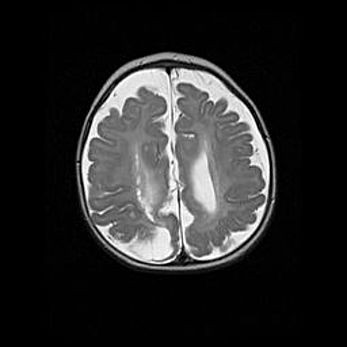

Множественные кисты обоих полушарий головного мозга, наибольшая из них в правой затылочной области. Ассиметричная атрофическая гидроцефалия.

Возраст: 7 месяцев

Вес: 5660 г

Пол: мужской

Окружность головы: 41,5 см

Срок гестации: 28-29 недель

Кисты головного мозга развиваются в результате многоочаговых некрозов вещества мозга и возникают вследствие перенесенной перинатальной инфекции, менингитов, энцефалитов, асфиксии, родовой травмы, расстройств мозгового кровообращения различного генеза. Образованию кист в веществе головного мозга плодов и новорожденных способствуют такие факторы, как высокое содержание в нем воды, недостаточная (или отсутствие) миелинизация и слабая астроглиальная реакция на повреждение.

Кисты могут сочетаться с гидроцефалией и другими поражениями головного мозга.